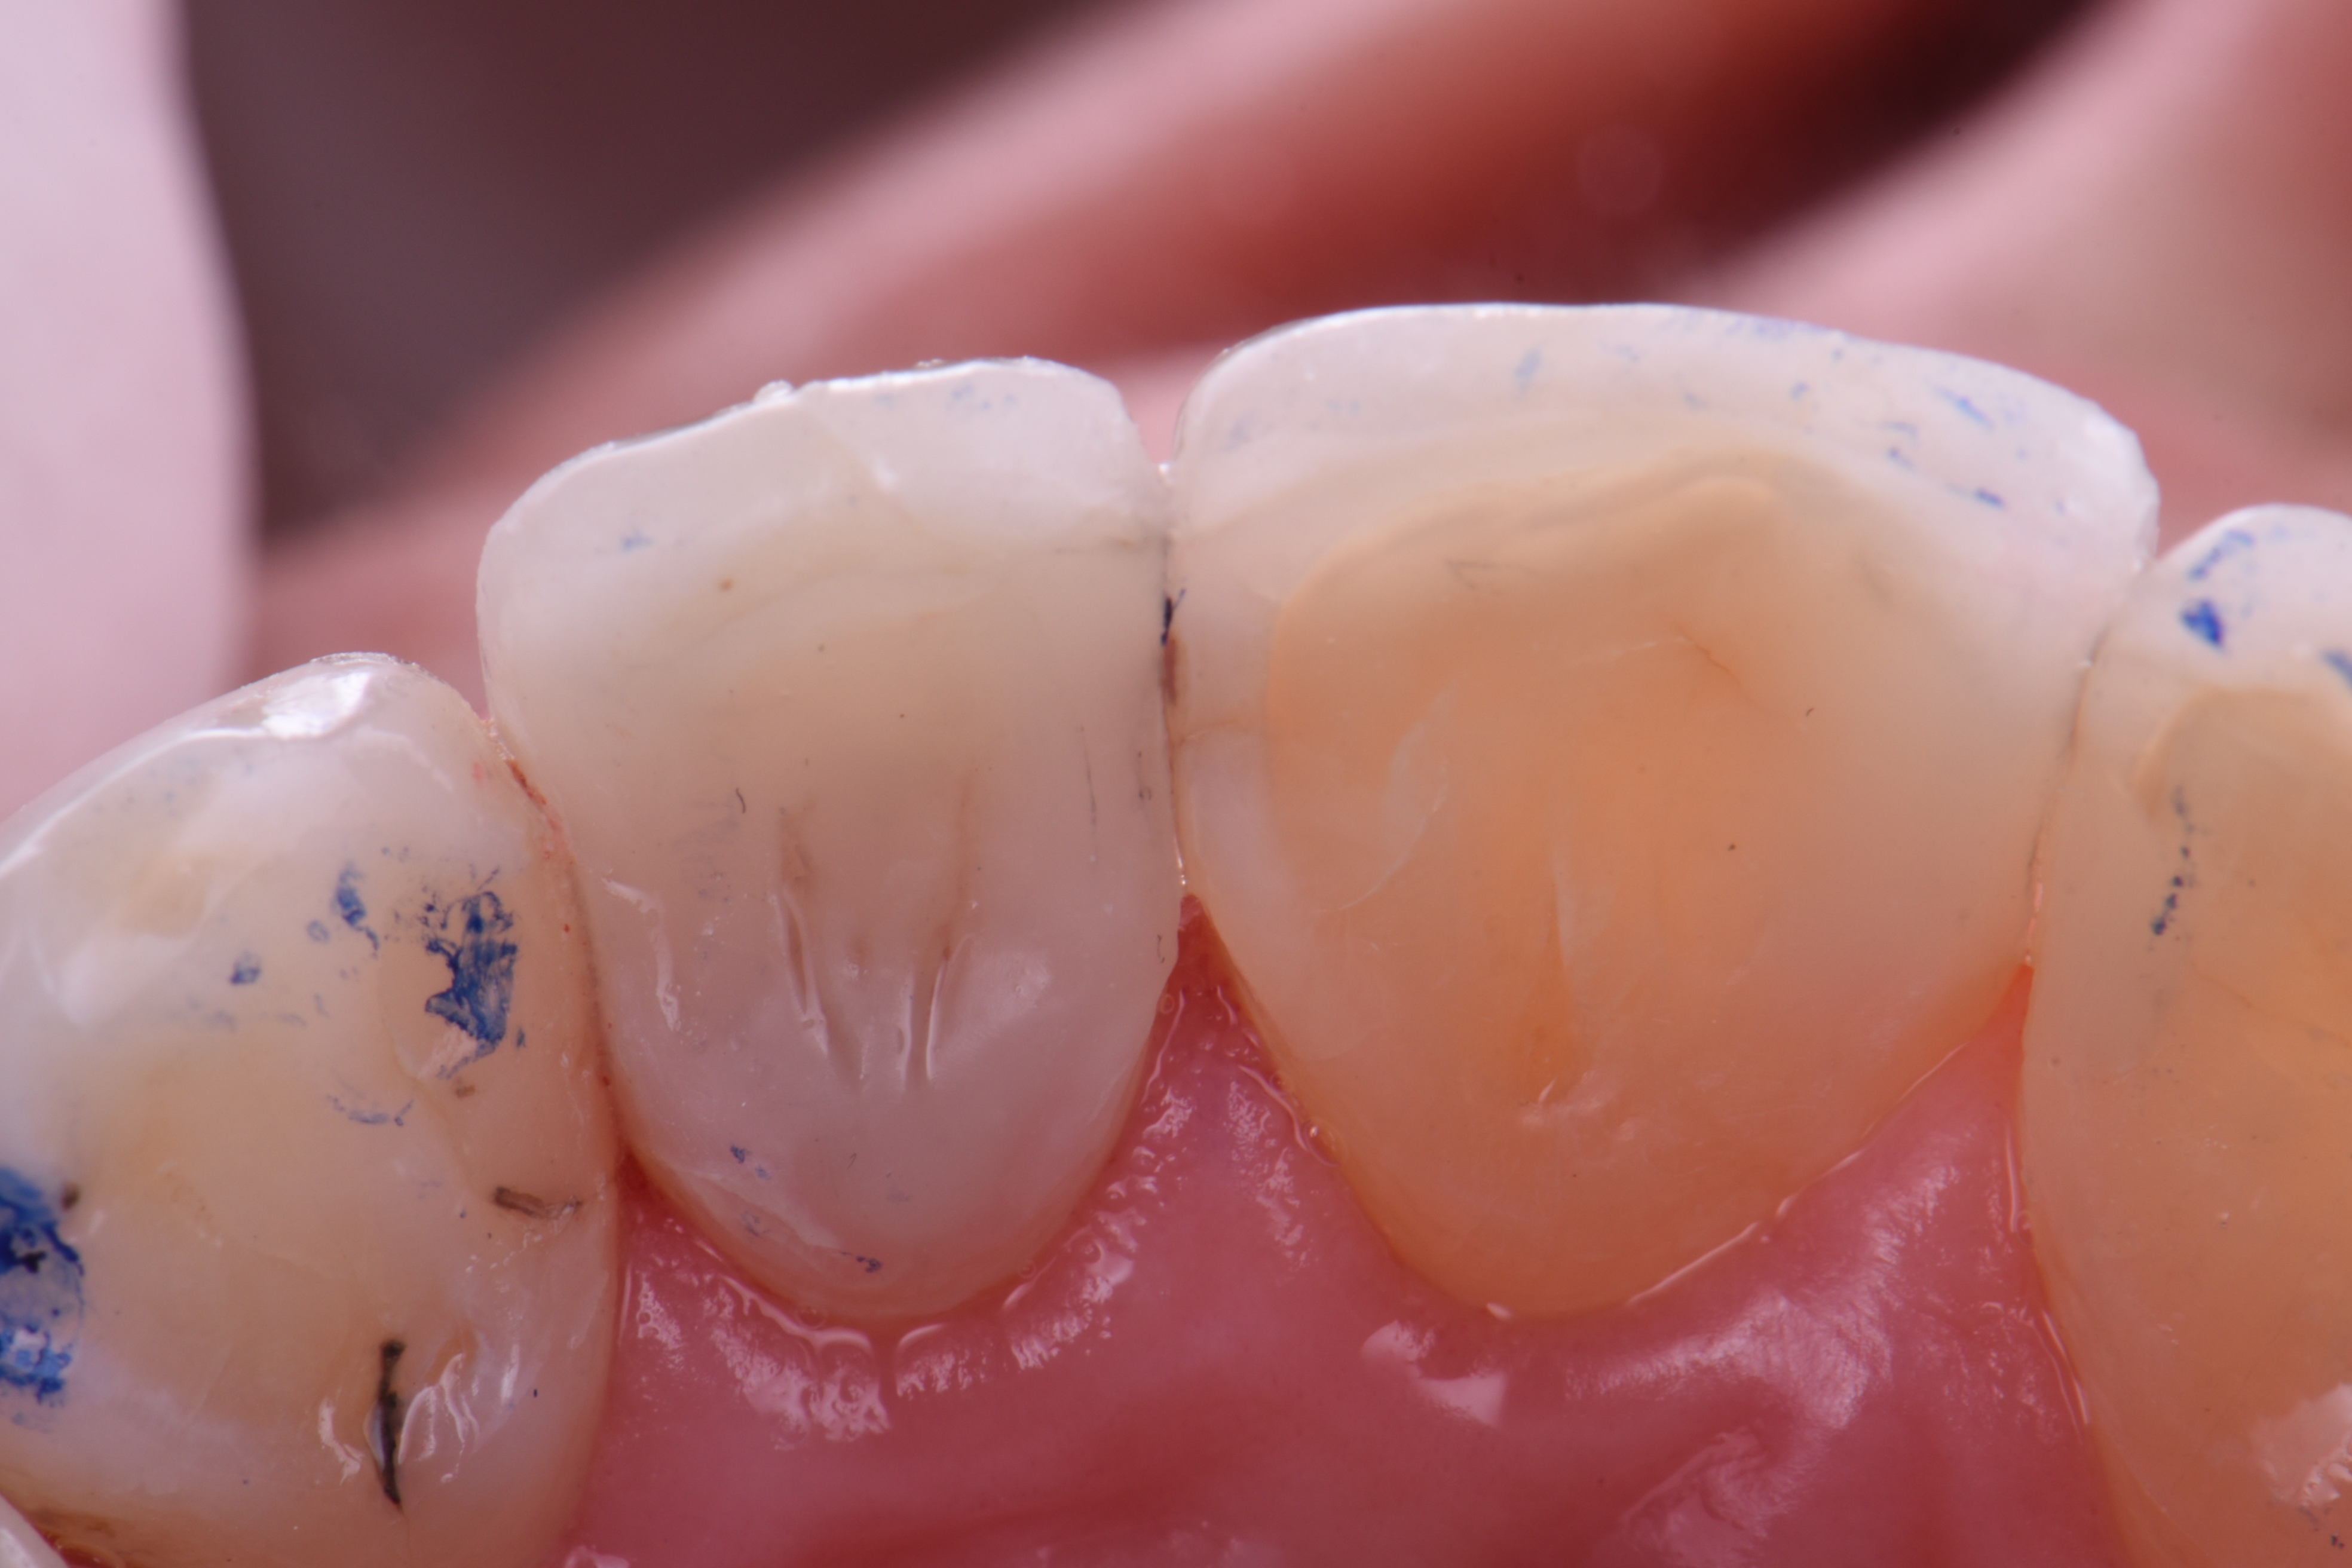

Una donna sana di 72 anni (classificata ASA II) si è presentata per la sostituzione protesica di vecchi restauri in composito su #7MP e DP e #8MP. I restauri risalivano a molto tempo prima e mostravano una forte infiltrazione marginale e, cosa interessante, erano appoggiati a delle vecchie faccette in porcellana feldspatica che la paziente desiderava conservare. La necessità di incollare su più substrati ha complicato il flusso di lavoro, i cui dettagli sono descritti di seguito. Il paziente è stato anestetizzato utilizzando 1 carpula di lignocaina al 2% con 1:100.000 epinefrina. Ciò avveniva prima che la diga di gomma fosse assicurata utilizzando singole fascette interdentali per ottenere la massima esposizione cervicale (Figura 1). Le preparazioni sono state completate con la rimozione delle carie ricorrenti, risultando in forme di contorno della preparazione che hanno coinvolto sia la porcellana feldspatica che lo smalto cervicale, il cemento esposto e, naturalmente, la dentina (Figura 2). Le preparazioni sono state smussate prima di essere sottoposte a micro abrasione ad aria utilizzando ossido di alluminio da 27 micron (Prep Start, Danville Engineering) impostato a 30-40 psi di pressione. La porcellana feldspatica è stata trattata con acido fluoridrico al 5% per 1 minuto prima del risciacquo e successiva applicazione di acido ortofosforico al 33% (Ultra-Etch, Ultradent Products) allo smalto per 10 secondi e prima di mordenzare la dentina per 12 secondi. La preparazione è stata completamente asciugata in questa fase prima dell’applicazione di un agente di accoppiamento silanico 10-MDP (G-MultiPrimer, GC America) alla porcellana feldspatica per 1 minuto. Anche in questo caso,la preparazione è stata asciugata all’aria essendo la porcellana preparata, ma non la dentina.

| Figura 1 | Figura 2 |